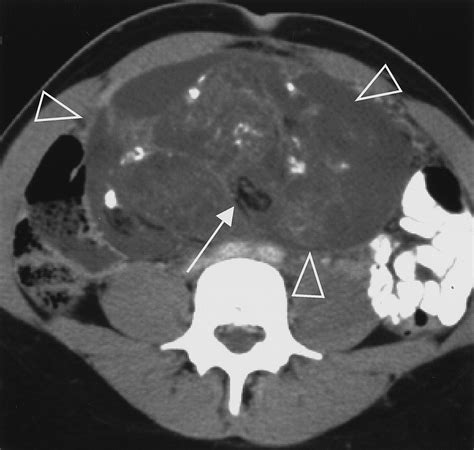

When doctors request scans, they are looking for specific visual identifiers. Imaging techniques such as CT scans, MRIs, and ultrasounds are standard. In these images, a teratoma often appears as a complex mass with both cystic (fluid-filled) and solid components. The presence of fat, calcifications (which look like bone or teeth on an X-ray), and soft tissue elements are hallmark signs that radiologists use to identify the growth.

While looking for Teratoma Cancer Pictures online, patients may see varying representations, but it is important to note that internal clinical imaging (like an MRI) looks significantly different from external surgical photography. Radiology provides the map for surgical intervention, helping surgeons understand the proximity of the tumor to vital organs.